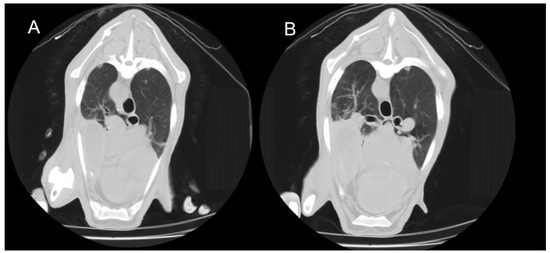

Use of Computed Tomography in the Clinical Diagnosis of Lower Respiratory Tract Diseases in Sheep

Lower airway diseases are a major health concern in sheep, often presenting with overlapping clinical signs that hinder accurate diagnosis. This study evaluated the diagnostic value of computed tomography (CT) in 58 adult sheep examined in northeastern Spain between 2017 and 2024. All animals underwent full clinical examination, CT under general anaesthesia, and post-mortem investigation. CT identified 82 pulmonary lesions, including interstitial pneumonia, respiratory complex, gangrenous pneumonia, caseous lymphadenitis, parasitic pneumonia, pulmonary adenocarcinoma, and pulmonary hydatidosis. Tissue density measurements provided additional information regarding disease stage and severity. The level of agreement between CT findings and definitive diagnoses consistently exceeded that of clinical evaluation, reaching almost perfect concordance for several conditions. Moreover, CT revealed concomitant respiratory pathologies within the same animal, many of which were not detected by conventional diagnostic methods. Although thorough individual clinical examination remains essential for the correct interpretation of imaging findings and the accurate diagnosis of respiratory disorders in the field, these results demonstrate that CT provides superior diagnostic accuracy compared with standard approaches and yields valuable insights for both clinical practice and research. Despite its practical limitations, CT could represent a major advance in improving health, welfare, and productivity in sheep farming. Full article